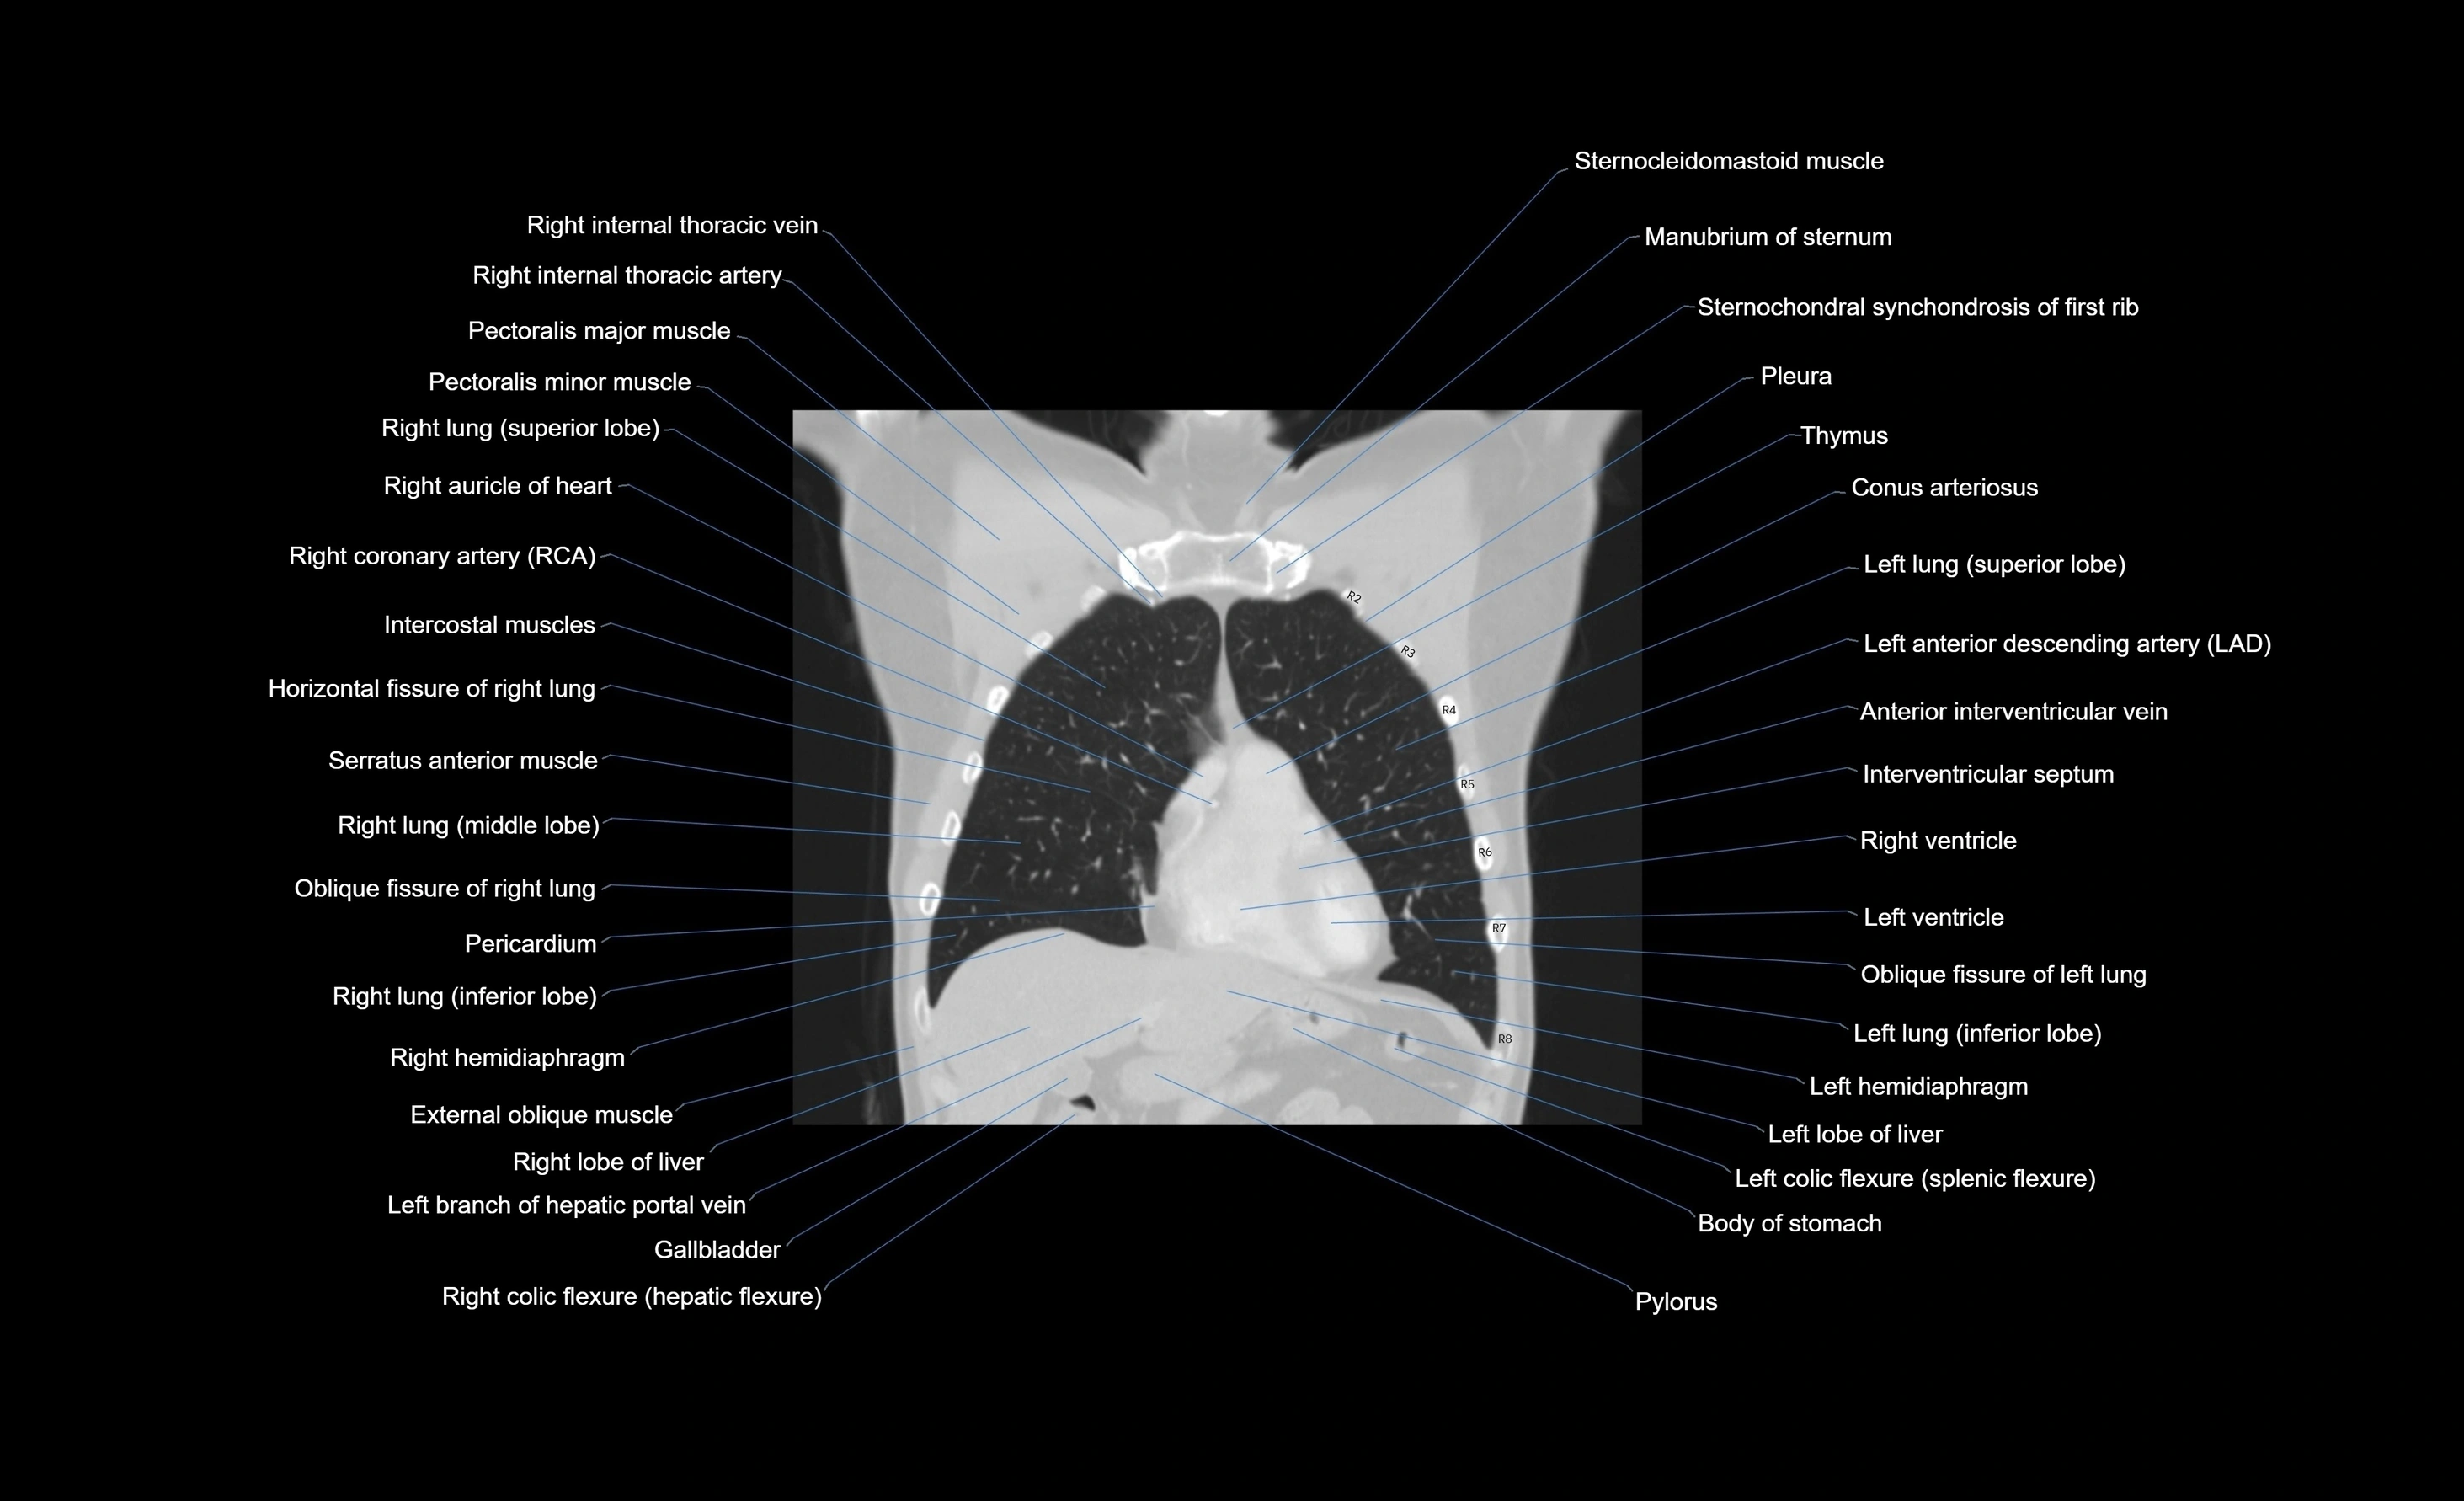

- Sternocleidomastoid muscle

- Manubrium of sternum

- Pleura

- Pectoralis minor muscle

- Pectoralis major muscle

- Right internal thoracic artery

- Right internal thoracic veins

- Right auricle of heart

- Right coronary artery (RCA)

- Intercostal muscles

- Horizontal fissure of right lung

- Serratus anterior muscle

- Right lung (middle lobe)

- Oblique fissure of right lung

- Pericardium

- Right lung (inferior lobe)

- Right hemidiaphragm

- External oblique muscle

- Right lobe of liver

- Hepatic portal vein

- Gallbladder

- Conus arteriosus

- Left anterior descending artery (LAD)

- Anterior interventricular sulcus

- Interventricular Septum

- Right ventricle

- Left ventricle

- Oblique fissure of left lung

- Left lung (inferior lobe)

- Left hemidiaphragm

- Left lobe of liver

- Transverse colon